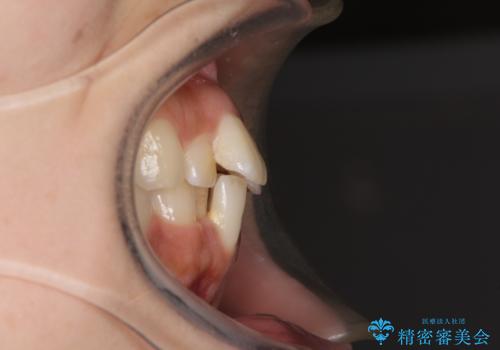

- 飛び出した前歯と全体的なデコボコを気にして来院された患者様です。

上下歯列全体を後方に移動させるため、親知らずは全て抜歯することにしました。